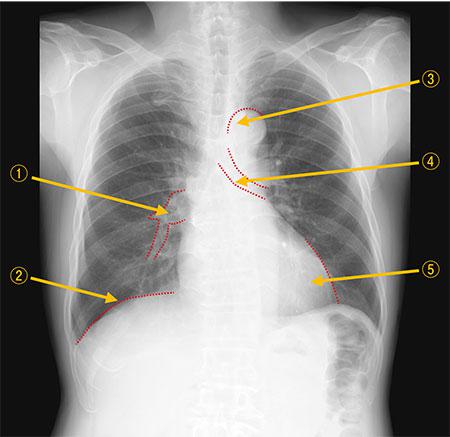

正常な胸部エックス線写真を示す。番号と解剖学的名称の組合せで正しいのはどれか。

1

①―肺静脈

2

②―肋骨

3

③―下行大動脈

4

④―気管支

5

⑤―左房縁